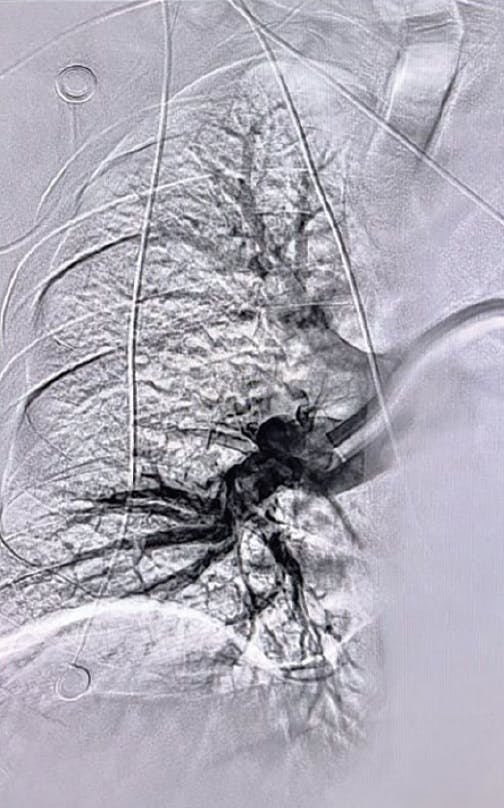

Figure 3. Right post-thrombectomy angiogram.

Figure 4. Left post-thrombectomy angiogram.

After initial evaluation, the decision was made to use aspiration thrombectomy to remove the PE thrombus. We utilized a 16-F, 65-cm Gore DrySeal sheath through the right femoral vein. Penumbra’s Lightning Flash was used for a device time of 10 minutes (Figure 3, Figure 4, and Figure 5). The total procedure time was only 20 minutes. With the conclusion of the case, we had an EBL of 120 mL and a postprocedure BP of 120/87 mm Hg. The HR decreased substantially to 98 bpm, and the oxygen saturation improved to 100% on room air.